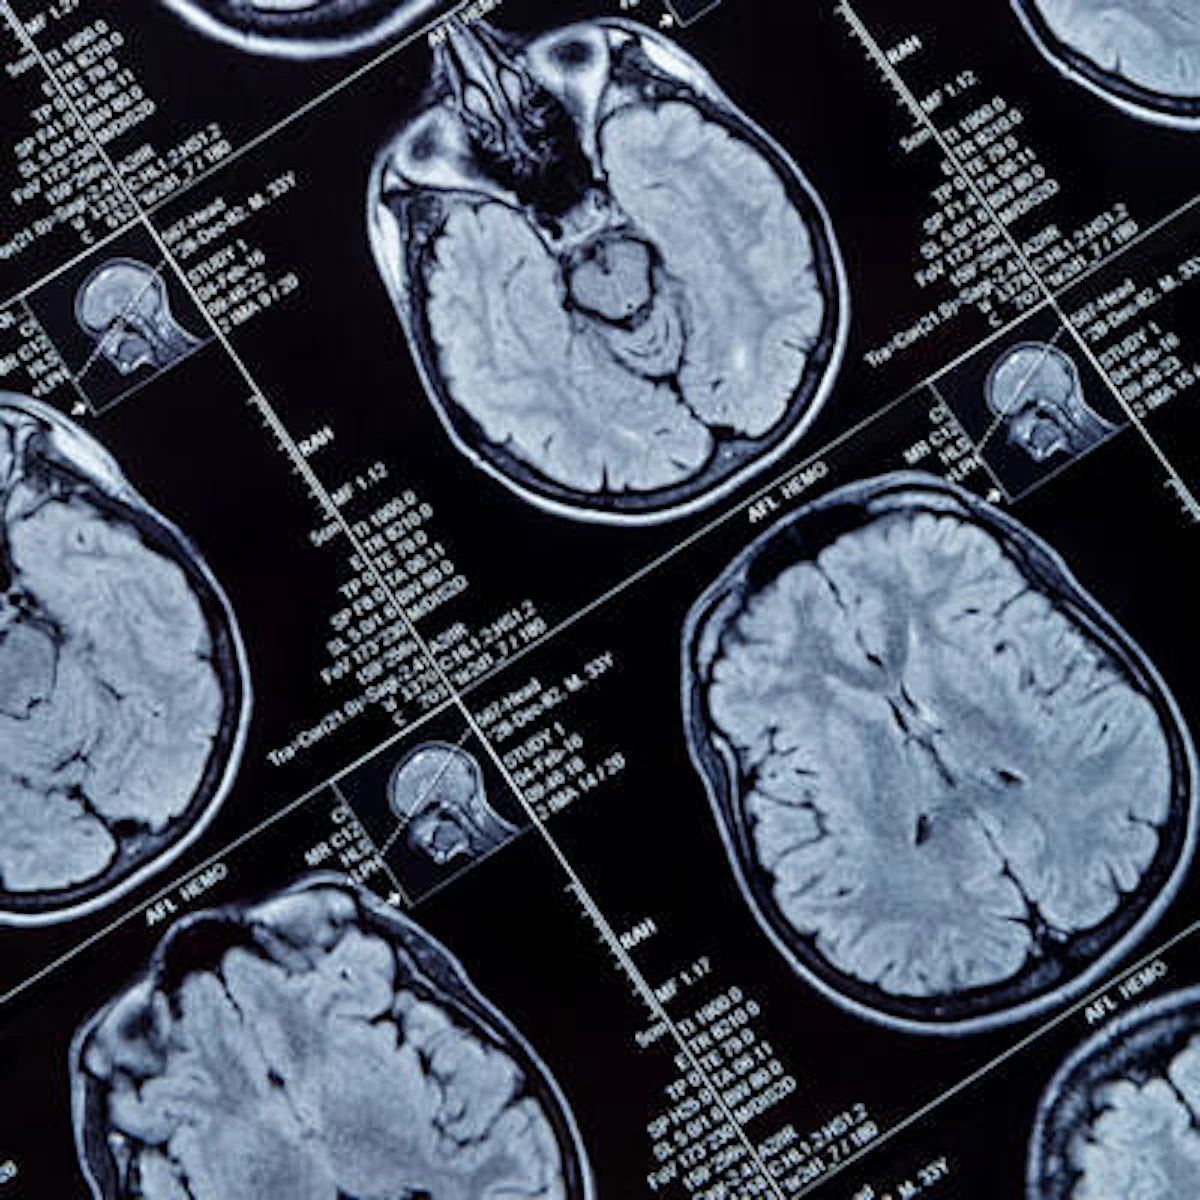

Here are some screenshots of head smart red flag criteria. If they are persistent and opticians haven't given an answer I would press for a scan. Looking at the criteria, she might meet the criteria for to the combination of headache and nausea, though in reality migraines are much more likely.

Incidental findings may be found on up to 21% of pediatric brain MRI exams, but most aren't dangerous, according to a study published March 22 in JAMA Neurology.